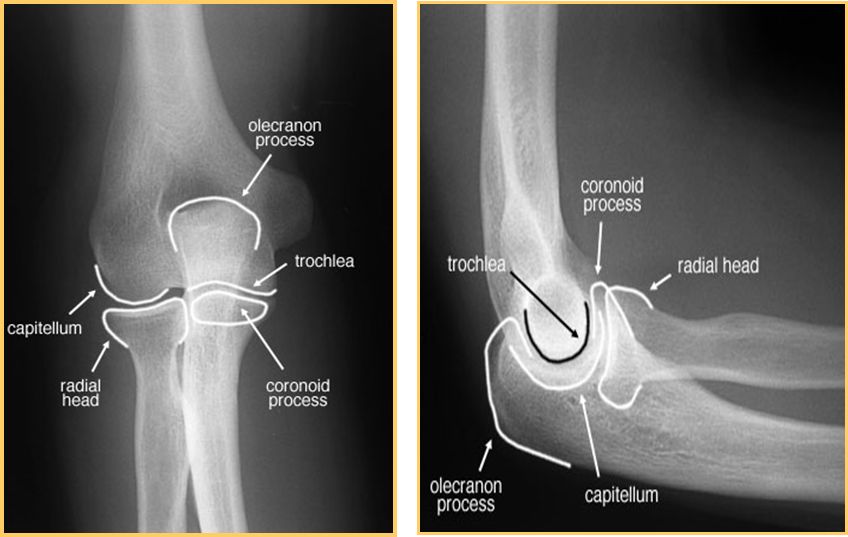

肱骨髁上骨折

肱骨髁间骨折

桡骨头骨折

前臂双骨折

孟氏骨折

尺骨骨折

桡骨头脱位

盖氏骨折